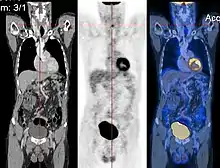

Image registration is a process that searches for the correct alignment of images.[21][22][23][24] In the simplest case, two images are aligned. Typically, one image is treated as the target image and the other is treated as a source image; the source image is transformed to match the target image. The optimization procedure updates the transformation of the source image based on a similarity value that evaluates the current quality of the alignment. This iterative procedure is repeated until a (local) optimum is found. An example is the registration of CT and PET images to combine structural and metabolic information (see figure).

- Combining complementary information from different imaging modalities. An example is the fusion of anatomical and functional information. Since the size and shape of structures vary across modalities, it is more challenging to evaluate the alignment quality. This has led to the use of similarity measures such as mutual information.[25]

The figure "Visualization of Medical Imaging" illustrates several types of visualization: 1. the display of cross-sections as gray scale images; 2. reformatted views of gray scale images (the sagittal view in this example has a different orientation than the original direction of the image acquisition; and 3. A 3D volume rendering of the same data. The nodular lesion is clearly visible in the different presentations and has been annotated with a white line.